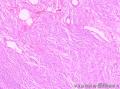

女;42岁,颈部乳头状瘤渐进性增大40余年;大小如鸡蛋大小

皮内痣,似乎有细胞散开倾向,痣细胞轻度不典型增生。

复合痣,痣细胞围绕着附属器生长,结合临床,考虑先天性色素痣,这里的图片异型性似乎不明显,成熟现象不十分典型,40多年病史了,皮损巨大,是否进一步做做免疫组化?

先天性色素痣

先天性色素痣 。